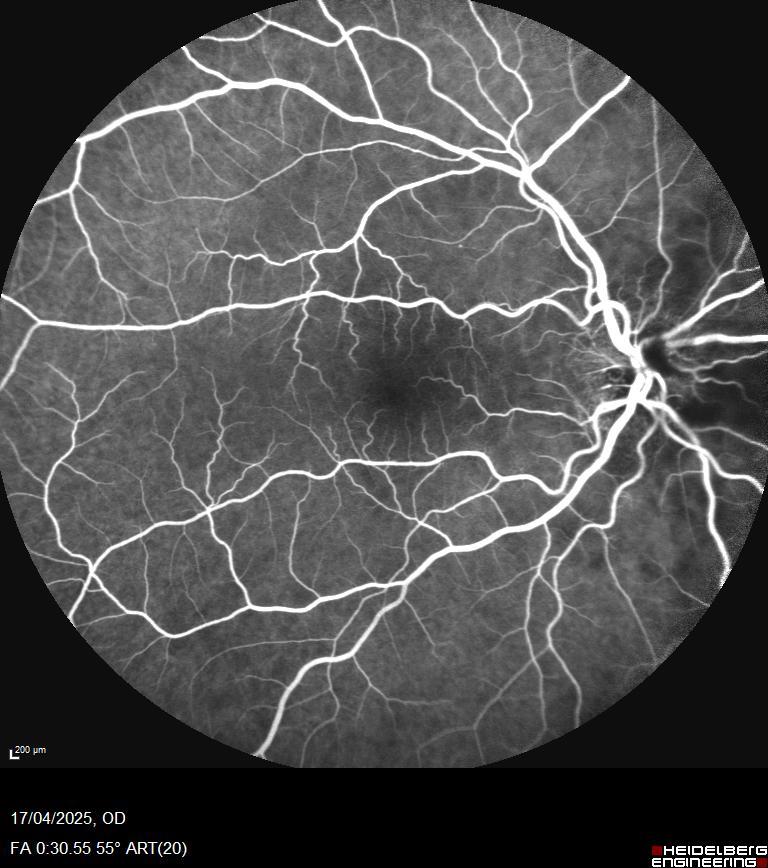

Eye fundus revealed an optic disc edema of the right eye that occurred to be pale of color

The fundus photograph reveals pallid disc swelling in conjunction with the clear vessel sign.  (Pollock SC, Arnold AC, Miller NR; Acta Ophth 97(7), 2019).

In an older individual, preservation of vascular clarity over the surface of an acutely swollen optic disc appears to be highly specific for GCA.  While the sensitivity of the sign has yet to be determined, it is not pathognomonic for arteritic AION, i.e., there are biopsy-confirmed cases that do not exhibit preservation of vascular clarity.  (An analogy with jaw claudication may be apropos  highly suggestive of GCA when present, but present only in a subgroup of GCA patients).

Given:  a) the patient's age; b) the ESR level; c) the CRP level; d) photographic and angiographic documentation of a sectoral choroidal filling defect from 3:00 to 4:00; e) pallid optic disc swelling; and f) preservation of vascular clarity over the surface of the swollen disc, a diagnosis of arteritic AION appears to be likely.